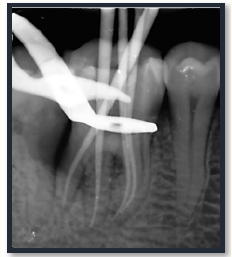

A Step-Ladder Approach for Management of Perio-Endo Lesion of a Radix Entomolaris: A Case Report

Sharayu Dhande, Nain Kharbe and Tejas Nalawade. 22(7): 30-40.